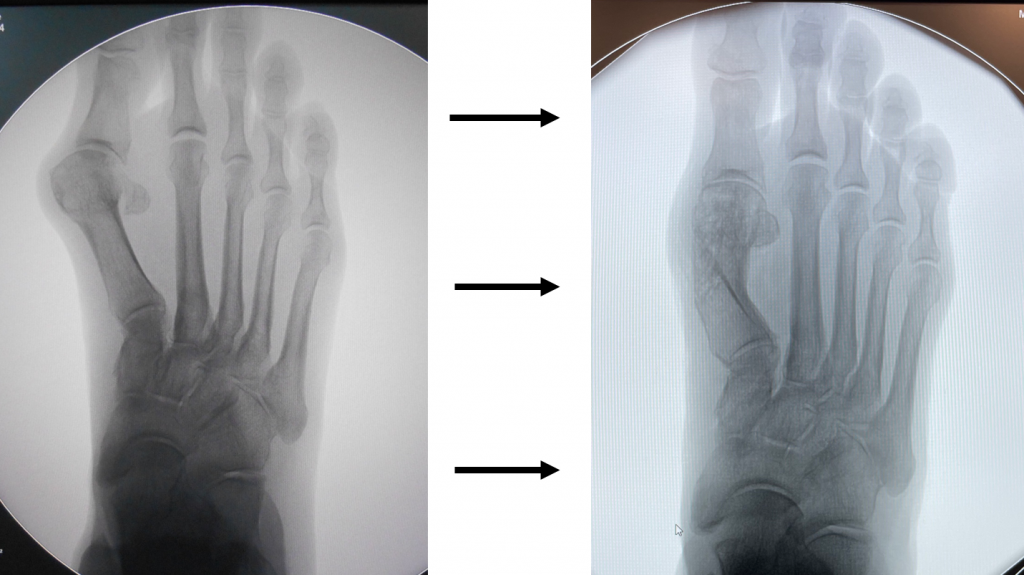

- primul metatarsian se sectioneaza complet, se translateaza si se re-pozitioneaza pe vechiul loc, deasupra sesamoidelor;

- fragmentele osoase se fixeaza cu mici suruburi speciale din Titan, facilitand consolidarea osoasa: se formeaza, in urmatoarele luni, nou os metatarsian.

- corectia deformatiei presupune schimbarea pozitiei osului deplasat catre pozitia sa initiala: primul metatarsian trebuie re-aliniat (re-axat) cu halucele ("degetul mare");

- practic, primul metatarsian se sectioneaza complet longitudinal, fragmentele osoase obtinute se translateaza unul fata de celalalt, iar partea distala a osului se re-pozitioneaza la locul sau initial, pe "soclul" sesamoidian;